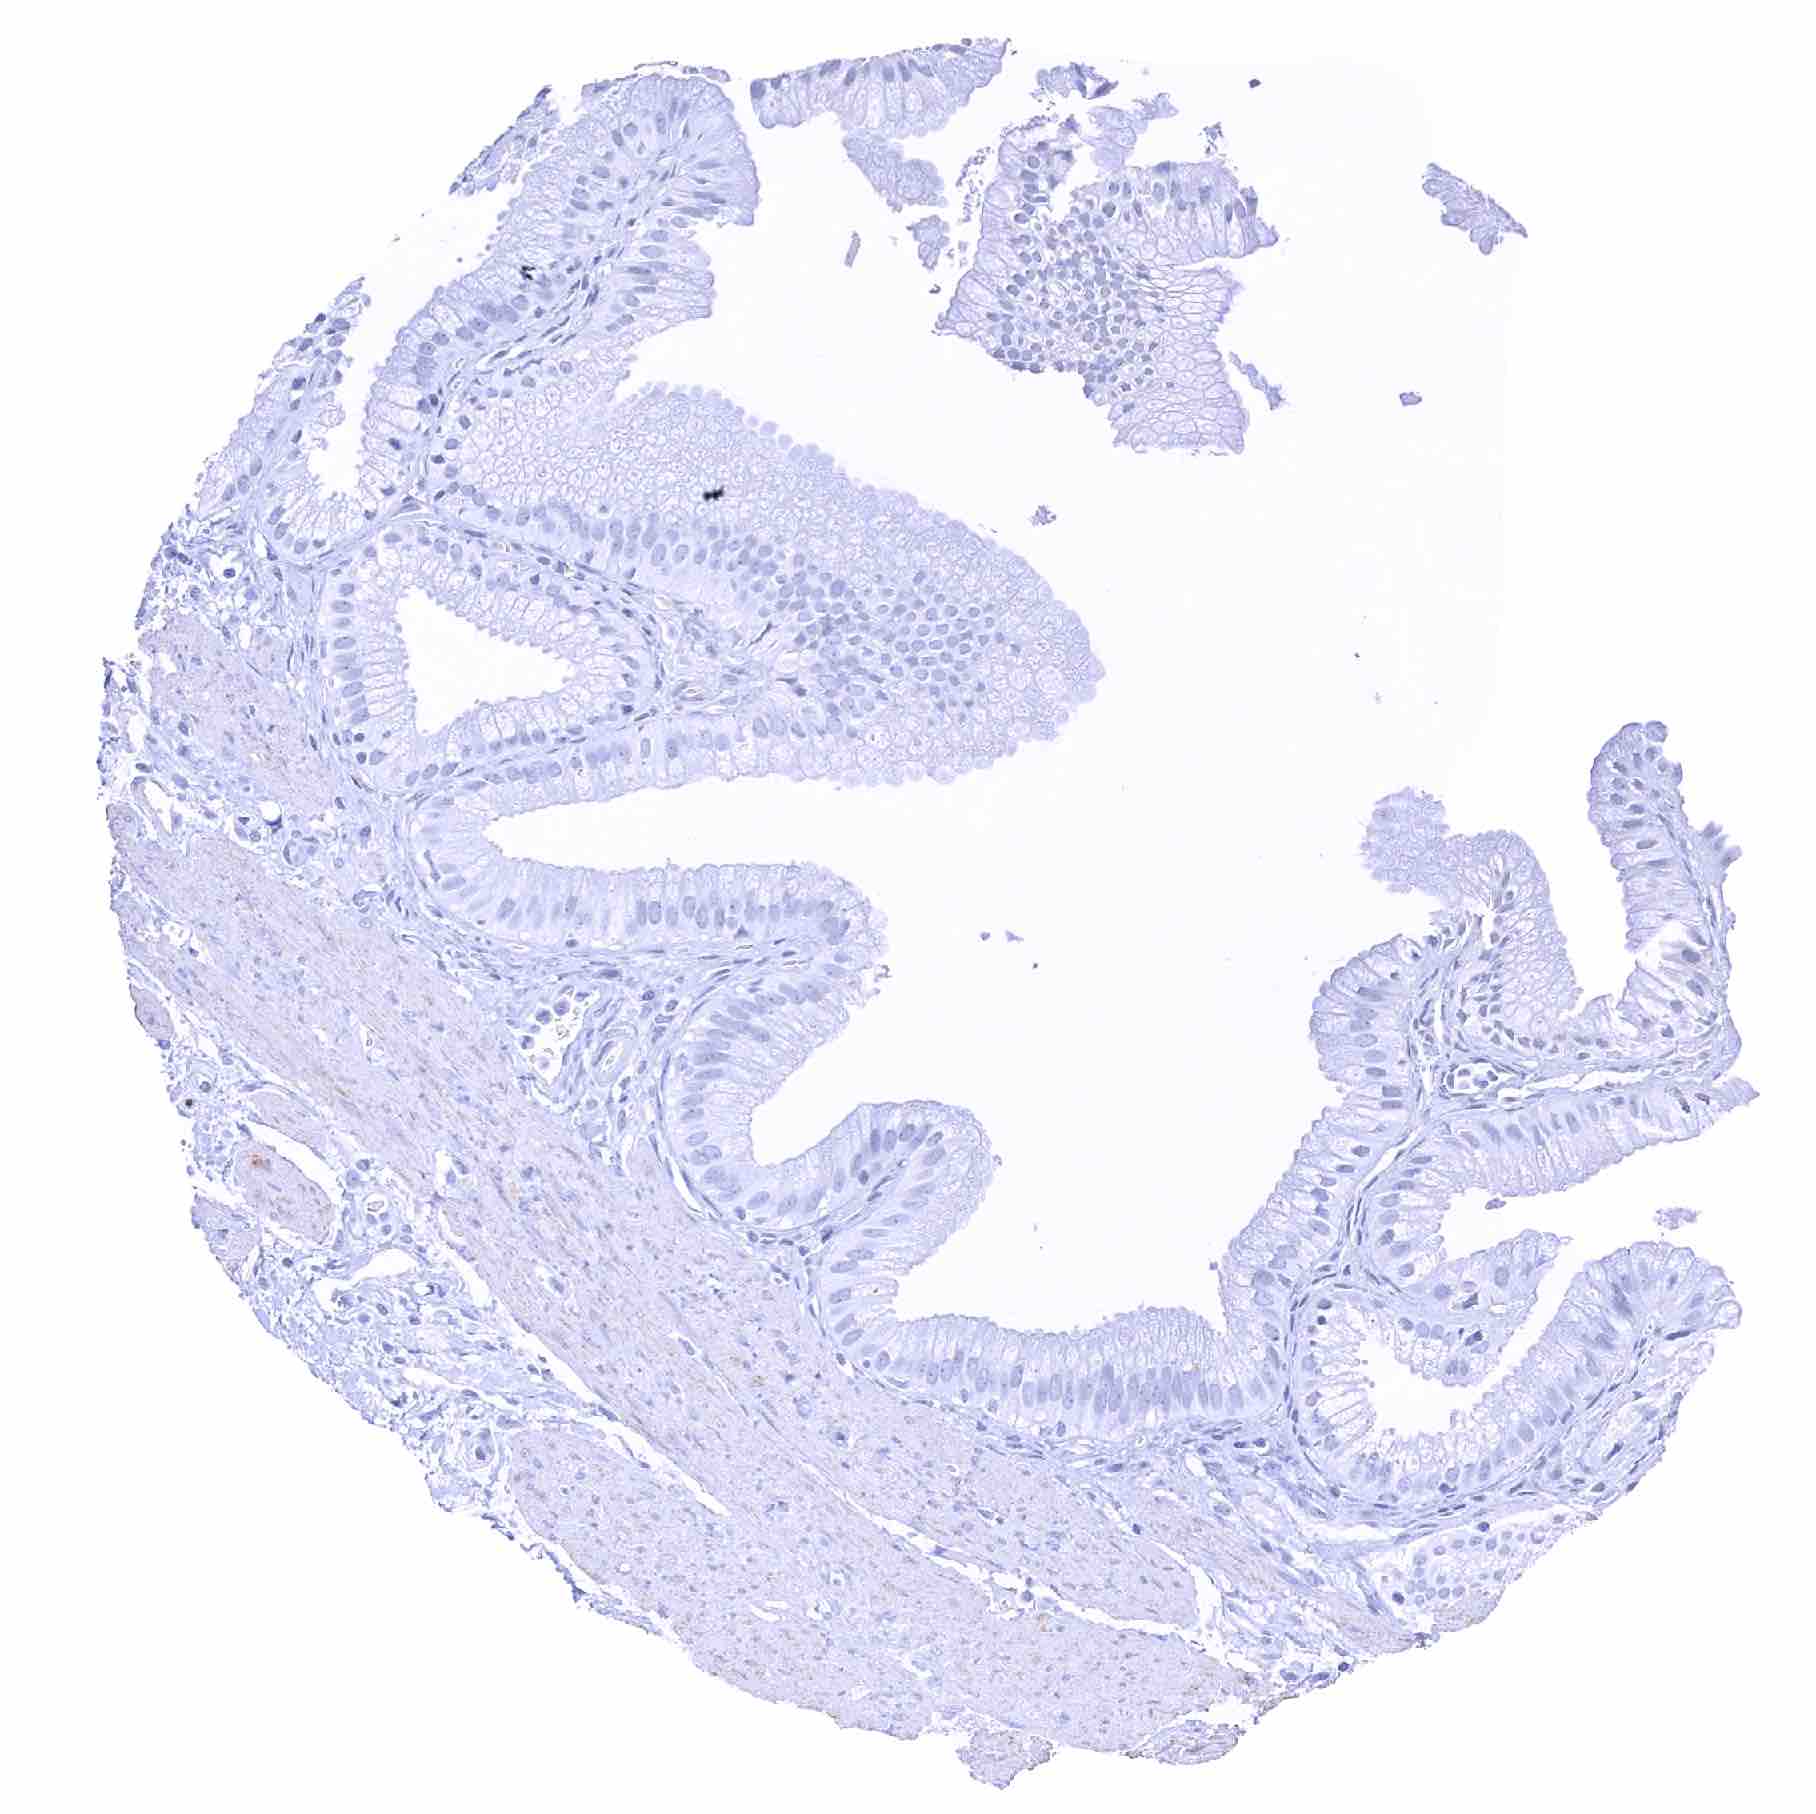

Colon descendens, mucosa

Colon descendens, muscular wall – Strong SOX2 positivity of a large fraction of intramural ganglion cells as well as of few spindle shaped (neural_) cells in the muscular wall